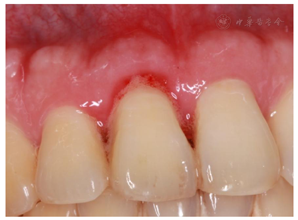

翻瓣探查术后3个月复查(2018年2月28日):检查:11舌侧暂封在,叩痛(-),Ⅰ-松动,唇侧龈退缩3 mm,牙龈充血,近中唇侧位点PD5 mm,余位点2~3 mm,见图6。X线片示:11近中骨质吸收已大部分恢复,见图7A。处置:11上橡皮障,3%次氯酸钠+生理盐水冲洗,干燥,Iroot SP+牙胶尖根充完成根管治疗见图7B,酸蚀粘接,树脂充填,调

,修形,抛光,完成治疗。